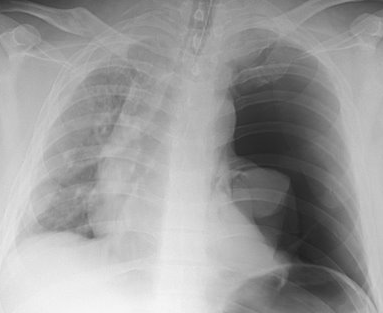

Rx toracică, incidență P-A

DESCRIERE:

la niv. întregului hemitorace drept → opacitate extinsă, nesistematizată, de intensitate mare, omogenă

caracter expansiv → împinge traheea și mediastinul de partea opusă

diafragm deplasat în jos

lărgirea spațiilor intercostale

umplerea spațiului costo-diafragmatic

DX: pleurezie masivă

DD: atelectazie → caracter retractil